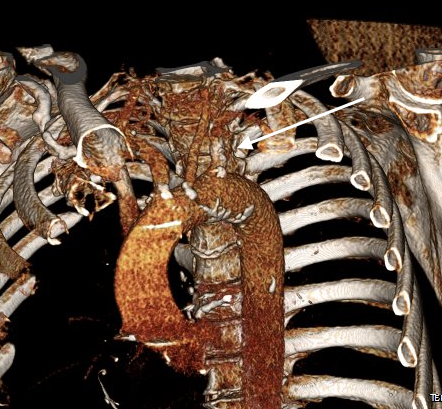

The EVAR was performed percutaneously. No endoleak was detected by completion arteriography (figure). He was soon discharged and was grateful. In followup, CT scan showed excellent coverage of the proximal and distal zones and absence of type III endoleaks. There was increased density to suggest a type II leak, but his inferior mesenteric artery was not the source of it. over a three year period, his aneurysm sac continued its 2-3mm of annual growth despite the presence of the the stent graft.

While CT failed to locate this endoleak, abdominal duplex ultrasound did showing flow from a small surface vessel (duplex below, figure at beginning of post). It was not the inferior mesenteric artery which can be treated endovascularly (link) or laparoscopically (link). CT scan suggested that it was one of those anterior branch vessels that one would encounter in exposing the aorta. Usually these were higher up as accessory phrenic arteries, but these fragile vessels, larger than vasovasorum, but smaller than named aortic branches, are seen feeding the tissues of the retroperitoneum.